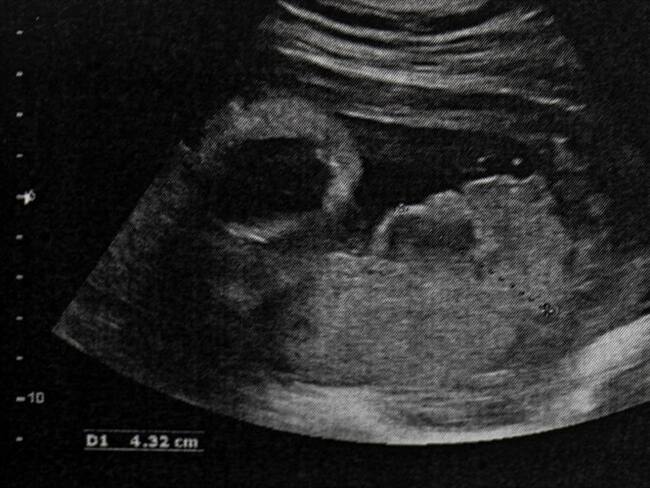

A su vez, la Corte debatirá sobre la despenalización del aborto después de esos cuatro meses si el embarazo representa un peligro inminente hacia la vida o la salud de la mujer “certificada por un médico, o si el embarazo es resultado de una conducta debidamente denunciada o, finalmente, si existe malformación del feto que haga inviable su vida”.